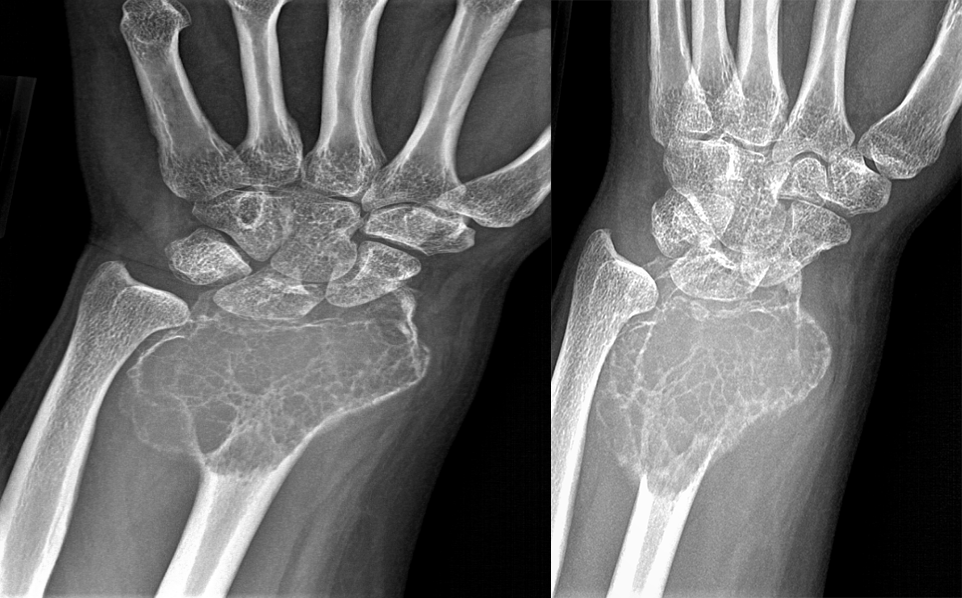

①骨巨细胞瘤:是一种潜在的恶性肿瘤。多发生于骺板愈合后的长管骨骨端,紧邻骨性关节面偏心性生长,横向膨胀性生长明显,呈皂泡样改变。

(注:女,20 岁,左侧桡骨干骺端见界限清楚、扩张性、偏心性、透明性病变,在桡骨骨骺处有内部分隔,延伸至干骺端并毗邻骨皮质。)

(注:患者一年后复查,可见膨胀性病变范围增加,现在延伸到整个桡骨下端,病灶主要以横向生长为主。)